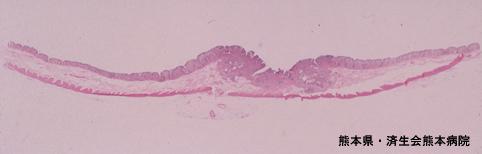

건강검진으로 발견된 조기대장암(증례제시:구마모토현, 사이세이카이 구마모토병원, Dr.요시다)

[Image-ID:4069]

악성 상피성종양/선암

대장/횡행

마이크로

0형(표재형)/IIa형(IIa+IIc)

20~24

sm